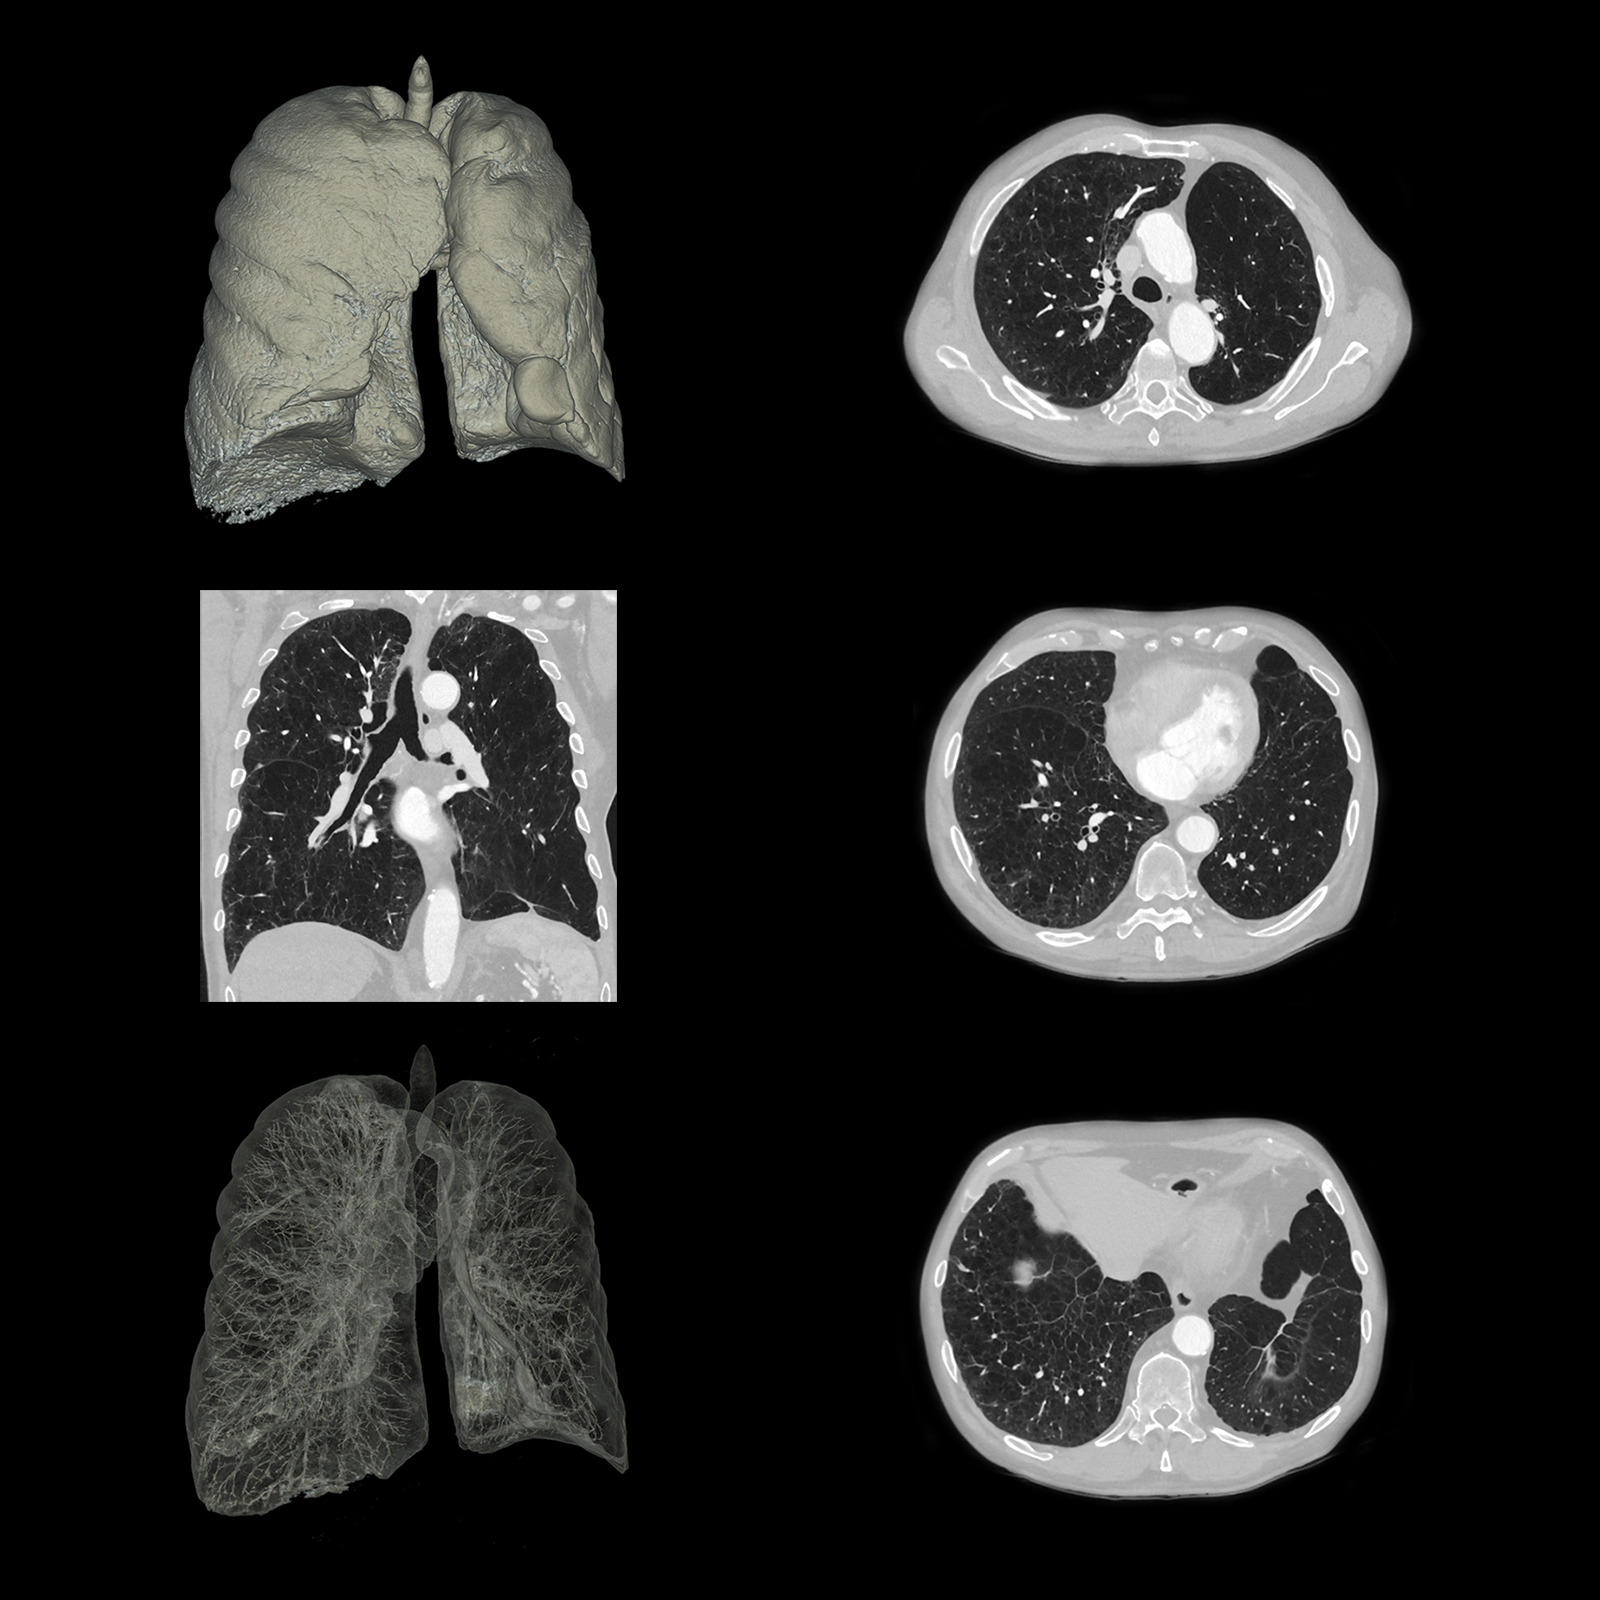

Фильтр SilverBeam

SilverBeam, энергетический фильтр, формирующий луч, использует свойства серебра по ослаблению фотонов для выборочного удаления фотонов низкой энергии из полихроматического рентгеновского луча, оставляя энергетический спектр, оптимизированный для скрининга рака легких.

КТ-скрининг рака легких при уровнях доз, приближающихся к обычной рентгенографии

Разработанный для работы в сочетании с AiCE, SilverBeam предоставляет улучшенные, высококачественные, малошумящие КТ-снимки скрининга рака легких при дозе облучения порядка типичного рентгенологического исследования грудной клетки.

SilverBeam с AiCE можно использовать для надежной организации службы скрининга рака легких в вашей больнице.